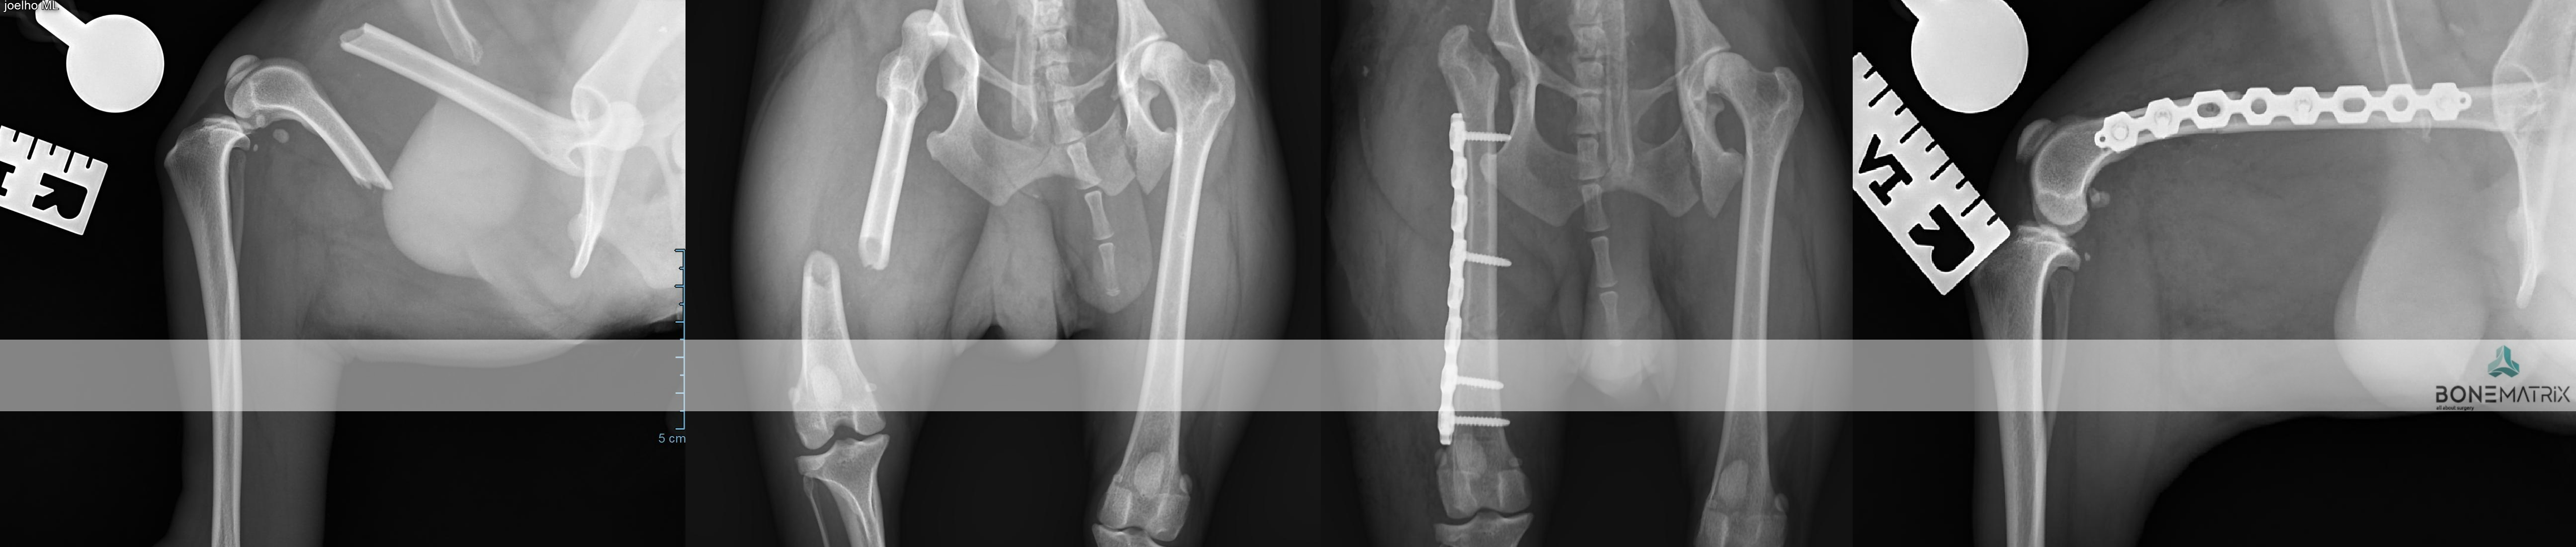

A traumatologia é o campo da cirurgia ortopédica que se dedica ao estudo e reparação de fracturas ósseas. Esta área de especialidade foi a base do nosso “case load" durante quase 10 anos.

Apresentamos uma vasta experiência na resolução destes casos com excelentes resultados.

No centro de cirurgia avançada abordamos qualquer tipo de casos de traumatologia, desde fraturas simples às mais complexas.

Em baixo poderá consultar algumas das técnicas realizadas neste tipo de casos, desde abordagens convencionais até às soluções mais extremas de salvamento do membro.